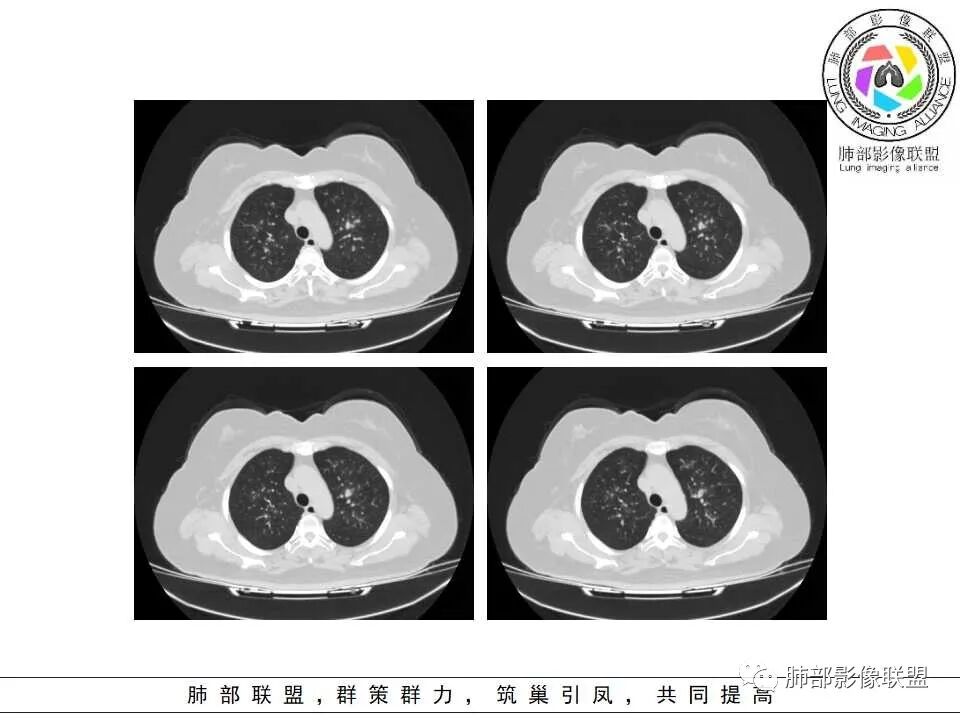

慢性病程,双肺支气管管壁增厚,周围可见多发点片状高密度影,边缘模糊不清,考虑气道侵袭性曲霉菌病

两肺支气管管壁增厚,沿支气管斑点状及斑片状高密度影,边缘模糊,考虑气道侵袭性曲霉菌,鉴别金葡萄、铜绿

中老年女性,气道分布的病变,有树芽树雾征,有支气管粘液栓,还有支气管壁增厚,考虑感染性病变,ABBA可能性大,鉴别支原体及军团,支原体以小孩多见,症状轻影像重,发病年龄及影像都不符合,患者住一楼,开麻将馆有聚集性,场地潮湿,不能排除军团肺炎!综合考虑ABBA,不排除军团

月亮圆了!:

糖尿病,血糖控制不好,气促,炎症反应明显(白细胞,crp明显升高,Gm(+)。气道分布的结节磨玻璃密度影,树芽,气管壁增厚。曲霉的可能最大

两肺叶支气管壁增厚,边缘模糊,见多发树芽及腺泡结节,边界不清,非对称性分布,CRP和WBC显著增高,抗炎无效,急性过敏性肺泡炎,与曲霉菌鉴别。

1.病灶沿支气管分布的特点相当明显,相应支气管壁广泛增厚。这种与支气管关系极为密切的片影和/或结节影,常高度提示气道相关感染,如支气管肺炎。

3.支气管壁广泛增厚对气道侵袭性曲霉病具有一定的提示意义。注意患者没有支气管扩张,临床也未提供IGE等实验室资料。

一,气道侵袭性曲霉病(PNTA)

1.器官支气管管套样壁增厚和/或支气管扩张,注意壁增厚较均匀,和/或伴有播散性小片影及结节影,注意这些小片影或结节影边界有时较普通炎性病灶清楚。